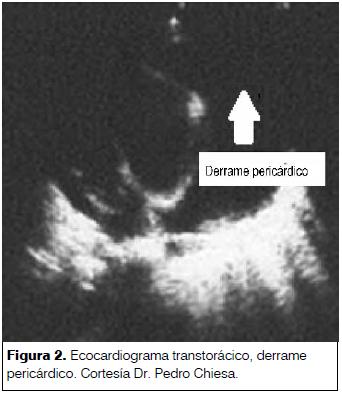

Se realizó radiografía de tórax en todos los pacientes. Se evidenció aumento de la silueta cardiopericárdica en 17 casos (FR 0,89), en dos casos no hubo alteraciones de la misma.

La radiografía de tórax constituye una herramienta diagnóstica. La misma orientó hacia la posibilidad de patología cardiopericárdica en 12 casos. Se debe tener presente que para evidenciar un incremento de la silueta cardiopericárdica (figura 1), el volumen del derrame debe ser de moderado a severo, por lo cual se arriba tardíamente al diagnóstico de pericarditis con derrame, incrementando el riesgo de complicaciones(6,13). El hallazgo de una silueta cardiopericárdica aumentada se presentó en 17 pacientes en la presente serie.